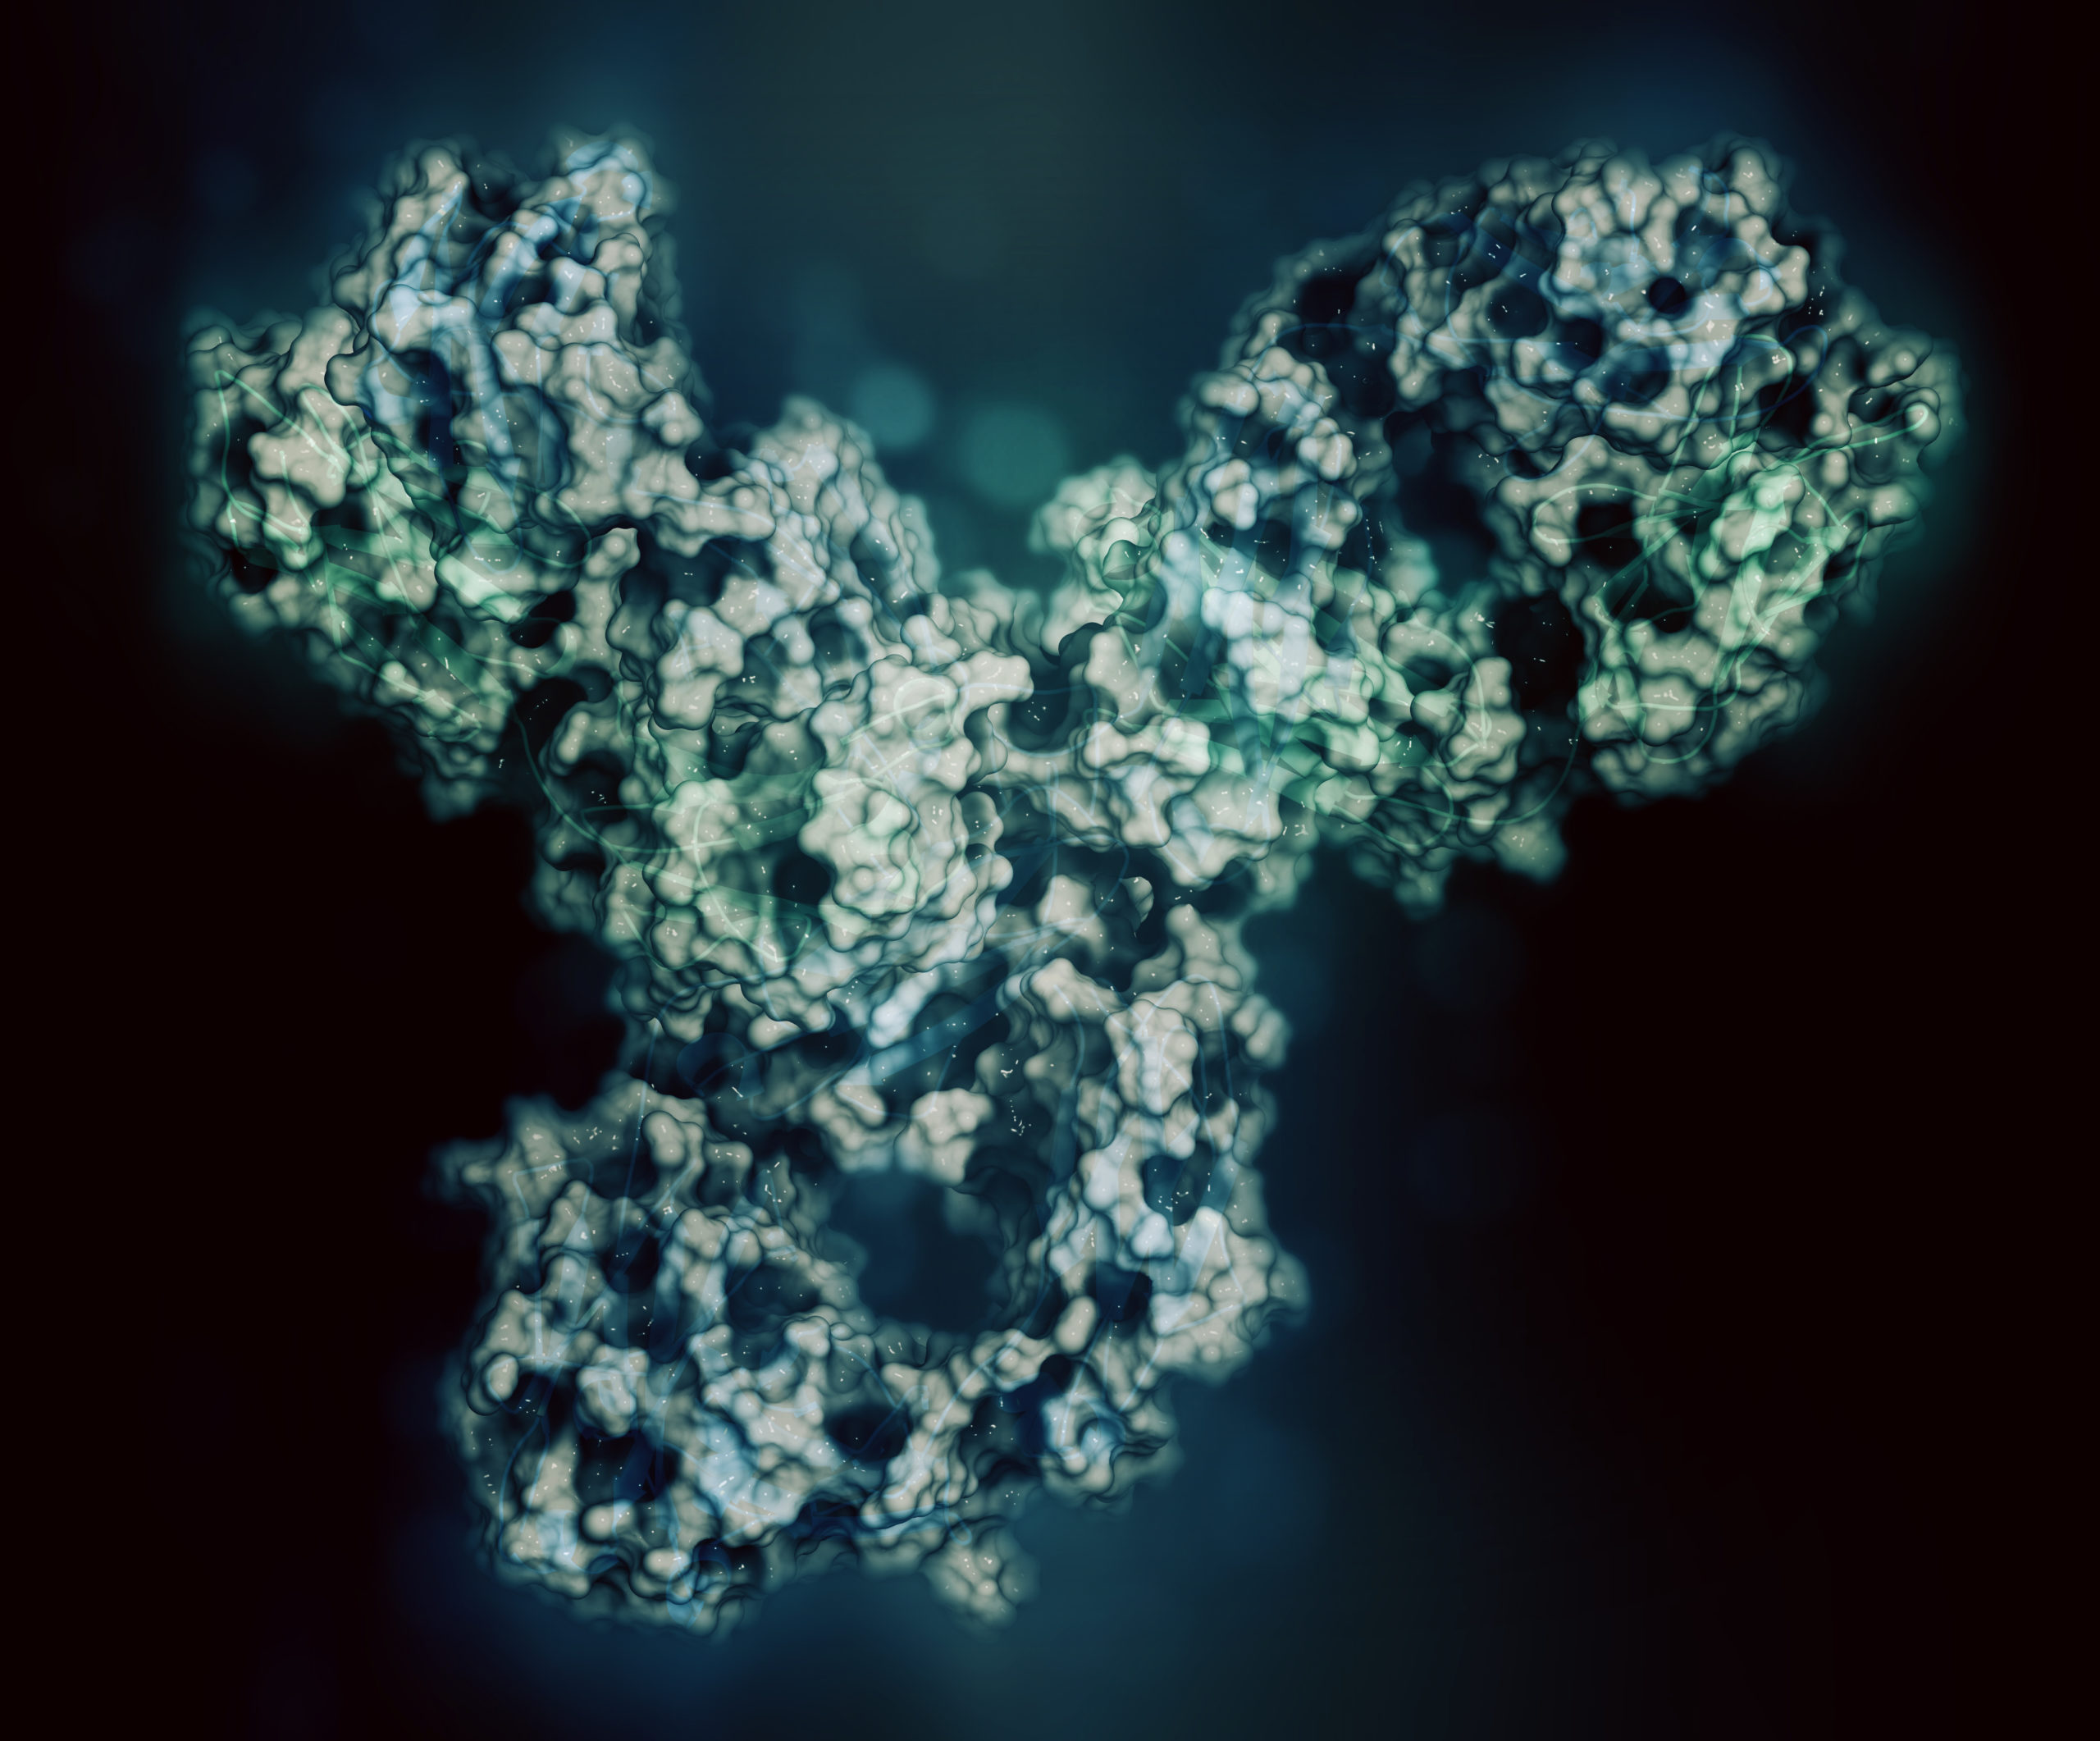

Immune checkpoint inhibitors (ICIs) are approved for treatment of small cell lung cancer (SCLC). However, according to ...

Adoptive cell therapy in combination with checkpoint inhibitors may be promising new treatment for patients with ...

A phase I/Ib study published in Clinical Cancer Research found that treatment with the immune checkpoint inhibitor ...